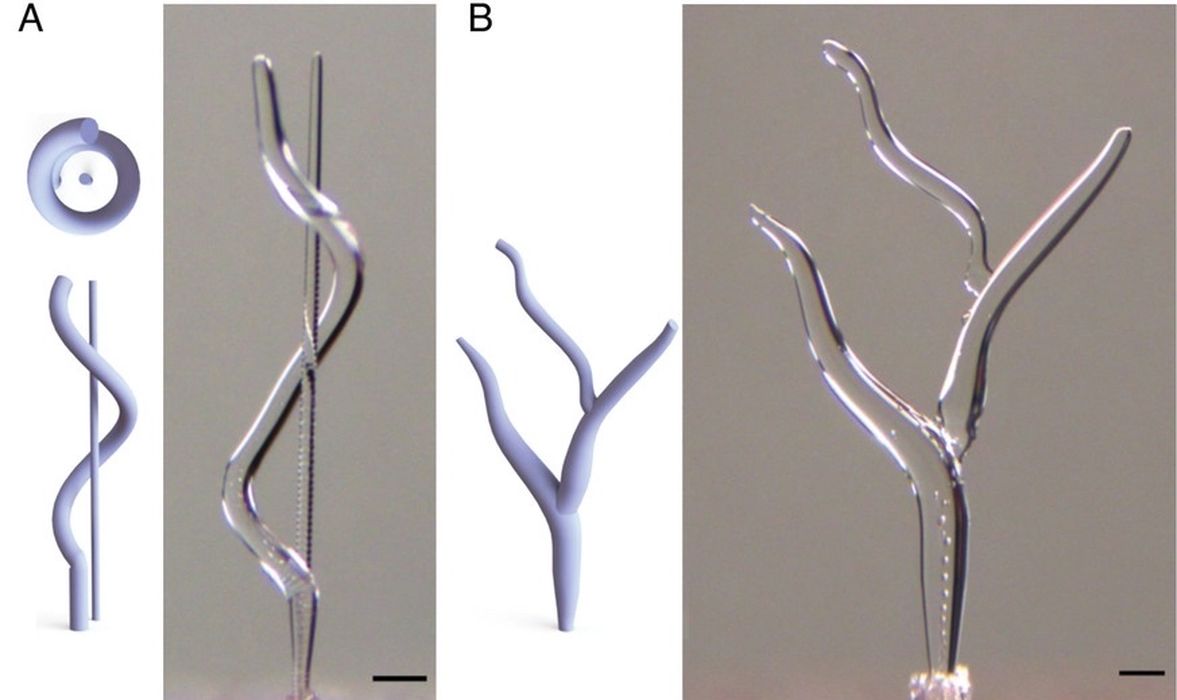

MIT’s MagMix Tackles Bioprinting’s Cell Settling Problem

MIT researchers have built a tiny magnetic mixer that keeps cells evenly suspended during extrusion bioprinting, looking to make printed tissues far more repeatable.